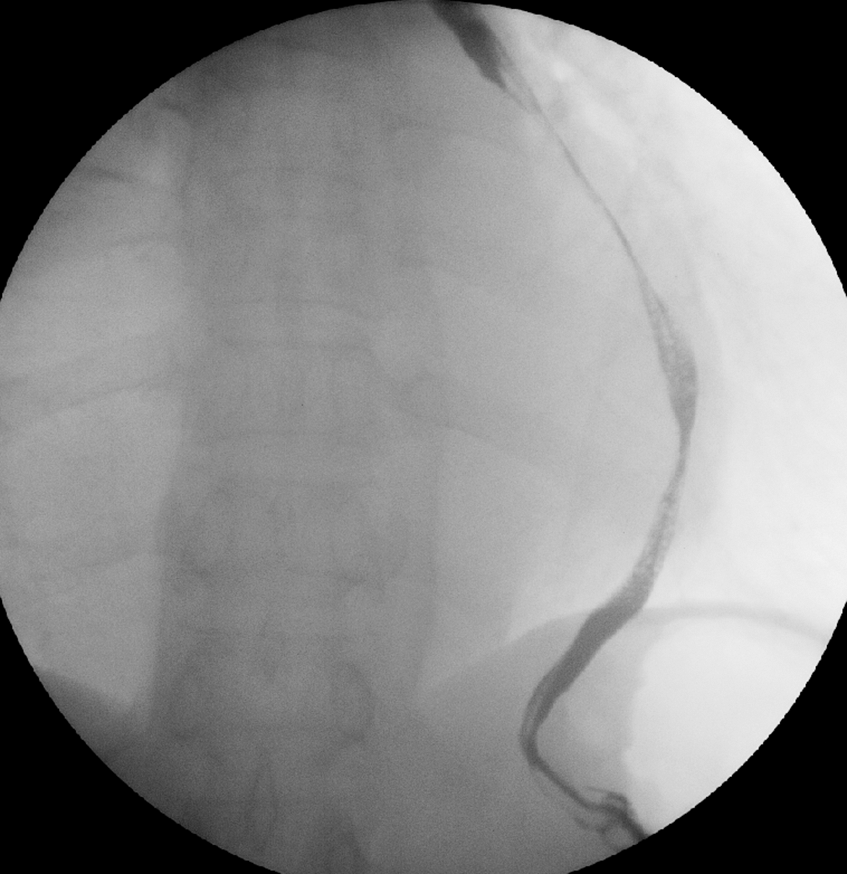

A 65-year-old man was referred to our hospital for investigation of atypical chest tightness of gradual onset over the previous 6 months. He denied weight loss, dysphagia, upper GI bleeding, reflux, or other symptoms. Blood and urine biochemistry showed almost normal results. However, transthoracic echocardiography revealed a solid echoic mass of approximately 16 cm behind the left atrium and significant compression of the left atrium. Chest computed tomography (CT) with contrast administration was performed. The examination was also completed by volume rendering reconstruction (VR) (Fig. 1) and revealed a solid mass of approximately 163 × 73 mm (the volume was 1308.92 mm3) visible behind the left atrium. The heart was compressed forward, the adjacent left atrium was significantly compressed, and the adjacent bronchi and esophagus were significantly compressed and displaced. A barium swallow study revealed that the lower esophagus was clearly shifted to the left under pressure, partially shifted forward in the left anterior oblique position, and shifted backward in the right anterior oblique position (Fig. 2). The barium meal passed smoothly. Considering that the patient had severe cardiac symptoms, thoracotomy was performed emergently. During the operation, the tumor was found to be approximately 17 cm in diameter and located in the posterior mediastinum, with unclear boundaries in some areas, abundant blood vessels on the surface, and cystic firmness in texture. The tumor was punctured with a thick needle to extract the internal fluid, which was bloody and mixed with sediment. After suction, the cyst wall was sutured and used for traction. The tumor wall was free along the edge of the tumor, with obvious oozing but no obvious blood-supplying artery. Because the source of the tumor was not known before the operation, the operation was very difficult. Further exploration on a subbase revealed that the tumor originated in the esophagus and had a short, wide pedicle on the lateral wall of the esophagus. Although the origin of the tumor has been clarified thus far, it is still difficult to completely remove the tumor. Fortunately, the entire tumor was finally removed with difficulty from meticulous operation. Postoperative pathological examination showed that the tumor was grayish yellow in section, had cystic firmness, was soft in quality and yellowish and sticky and frozen in appearance; part of the gray matter was broken, and part of the envelope was yellowish dark red. The diagnosis was an esophageal gastrointestinal stromal tumor with nuclear division <5/50 HPF (Fig. 3). The tumor basal margins were negative, and lymph node examination showed no cancer metastasis. Immunohistochemical indicators were as follows: SMA (−), S-100 (−), actin (+), desmin (−), PCK (−), EMA (−), VIM (+), CD34 (+), c-kit (+), Dog-1 (+), MDM-2 (+), CDK4 (−), and KI67 (+4%). After a multidisciplinary meeting, the patient received adjuvant therapy. Through multidisciplinary consultation, the patient received oral treatment with 400 mg of imatinib once daily after the operation and was closely followed up with chest CT scans (Fig. 4) or the barium esophagram every 6 months. After 3 years, the patient showed no sign of local recurrence with regular barium esophagram (Fig. 5), and no abnormally enlarged lymph nodes shadows were found on CT scans of the chest and abdomen performed during the follow-up.

Figure 2: Barium esophagram revealed that the esophagus was clearly shifted to the left and was significantly narrowed